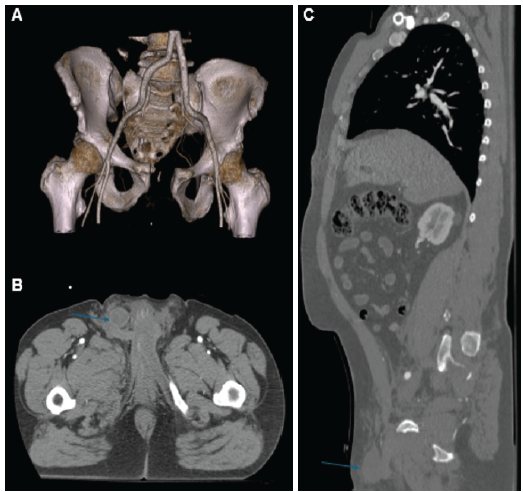

Two male patients (aged 51 and 40) were admitted following high-energy motor vehicle collisions in 2021 and 2024. Each sustained unstable pelvic ring injuries: One with a Tile C2 (AO 61-C2), and the other with a Tile B3 (AO 61-B3) fracture pattern. Time from injury to surgery was 48 h in both cases. Pre-operative computed tomography (CT) scan revealed right testicular dislocation into the pelvic cavity, anterior to the bladder, identifiable in axial and sagittal views (Figs. 1 and 2). Physical examination noted hemiscrotal asymmetry, but due to the patients’ polytrauma context, findings were not initially prioritized.

Figure 1: Preoperative computed tomography images from Case 1. (a) Three-dimensional reconstruction showing the pelvic fracture pattern. (b) Coronal view demonstrating migration of the right testicle into the pelvic cavity (indicated by a blue arrow). (c) Sagittal view confirming the presence of the testicle within the pelvic cavity (blue arrow).